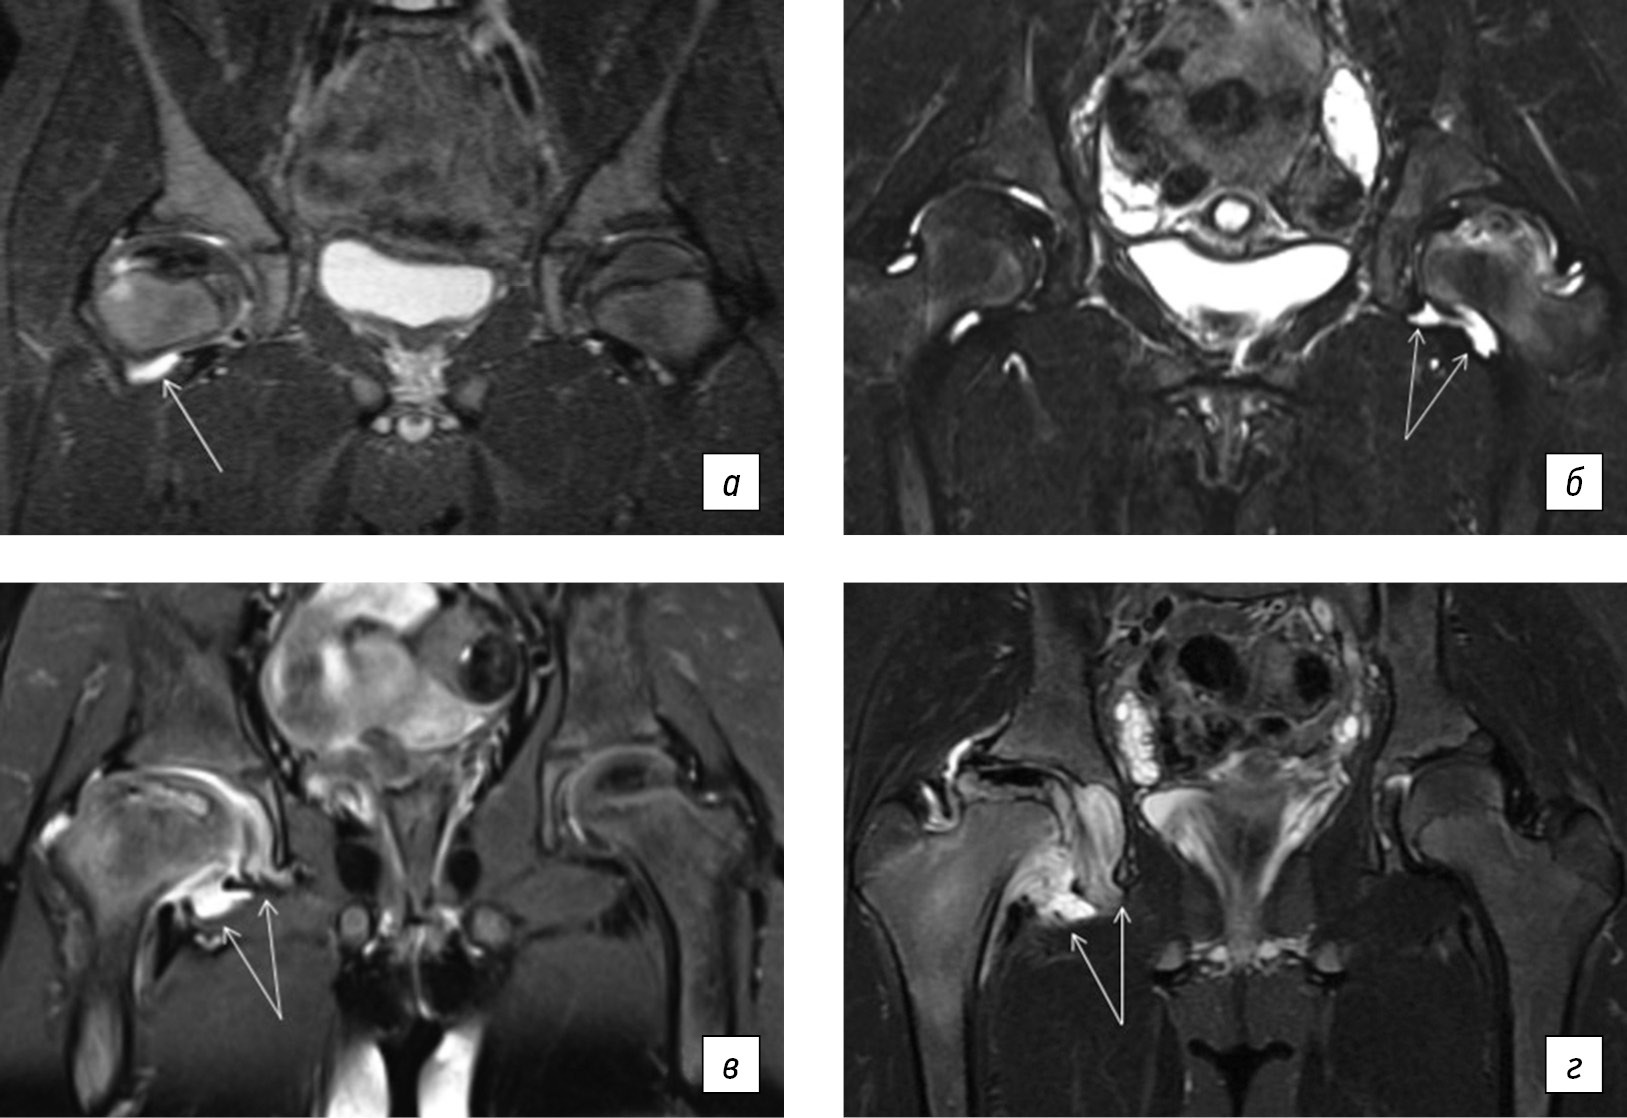

Тяжесть поражения головки бедренной кости оценивали по объему очага некроза и интенсивности трабекулярного отека прилежащих отделов костной ткани и выражали в балах, где 0 — отсутствие очага некроза и трабекулярного отека; 1 — объем очага некроза и зона трабекулярного отека занимают не более 33 % эпифиза; 2 — объем очага некроза и зона отека занимают 34–66 % эпифиза; 3 — объем очага некроза и зона отека занимают 67–100 % эпифиза (рис. 3). Таким образом, максимальное суммарное число балов — 6. Считалось, что остеоартрит с высокой степенью активности соответствует 5–6 баллам, умеренной активности — 3–4 баллам, низкой активностью — 2 баллам. Неактивная стадия остеоартрита у детей соответствует 0–1 баллу при условии отсутствия очага некроза (рис. 4). Лабораторный комплекс включал определение значений стандартных маркеров воспалительной активности и костного метаболизма, а также уровень кальпротектина, виментина, интерлейкина-6 (IL6), фактора некроза опухоли альфа (TNF-α) в сыворотке крови, титра антинуклеарного фактора (АНФ) на клеточной линии HEp-2 на момент верификации остеоартрита. Всем детям также проводили тестирование на наличие антифосфолипидного синдрома и гипергомоцистеинемии.

Рис. 3. Магнитно-резонансная томограмма: признаки различной тяжести поражения головки бедренной кости у детей с болезнью Легга – Кальве – Пертеса. На магнитно-резонансной томограмме в режимах STIR представлены: объем очага некроза и зона трабекулярного отека занимают не более 33 % эпифиза (а); объем очага некроза и зона отека занимают 34–66 % эпифиза (б); объем очага некроза и зона отека занимают 67–100 % эпифиза (в, г)